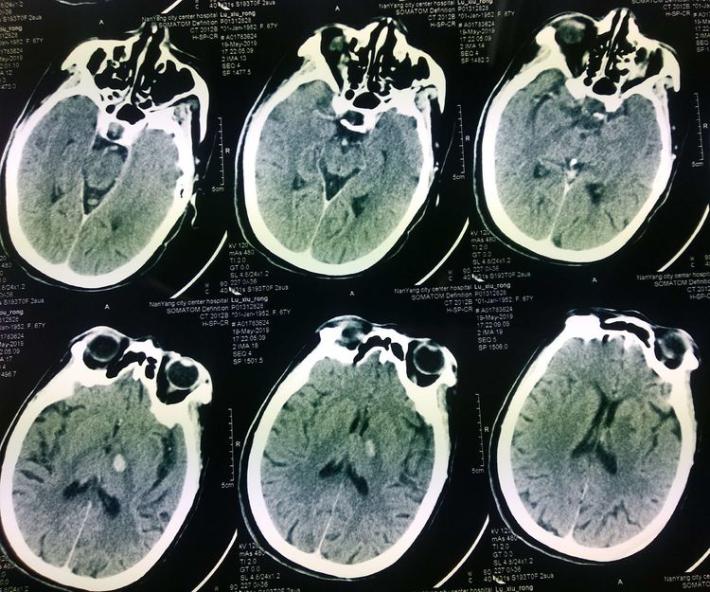

术后即刻复查头部CT

术中术后给予盐酸替罗非班应用12小时,桥接阿司匹林0.1g、氯吡格雷75mg,权衡利弊,未因核心梗死区出血转化停用抗血小板聚集药物。

患者术后1天,左侧肢体肌力0级,NIHSS评分:12分,复查头部CT:右侧基底节区出血,范围约22mmX49mm,请脑外科会诊:做好立体定向穿刺准备,注意观察患者病情变化,密集复查头部CT。